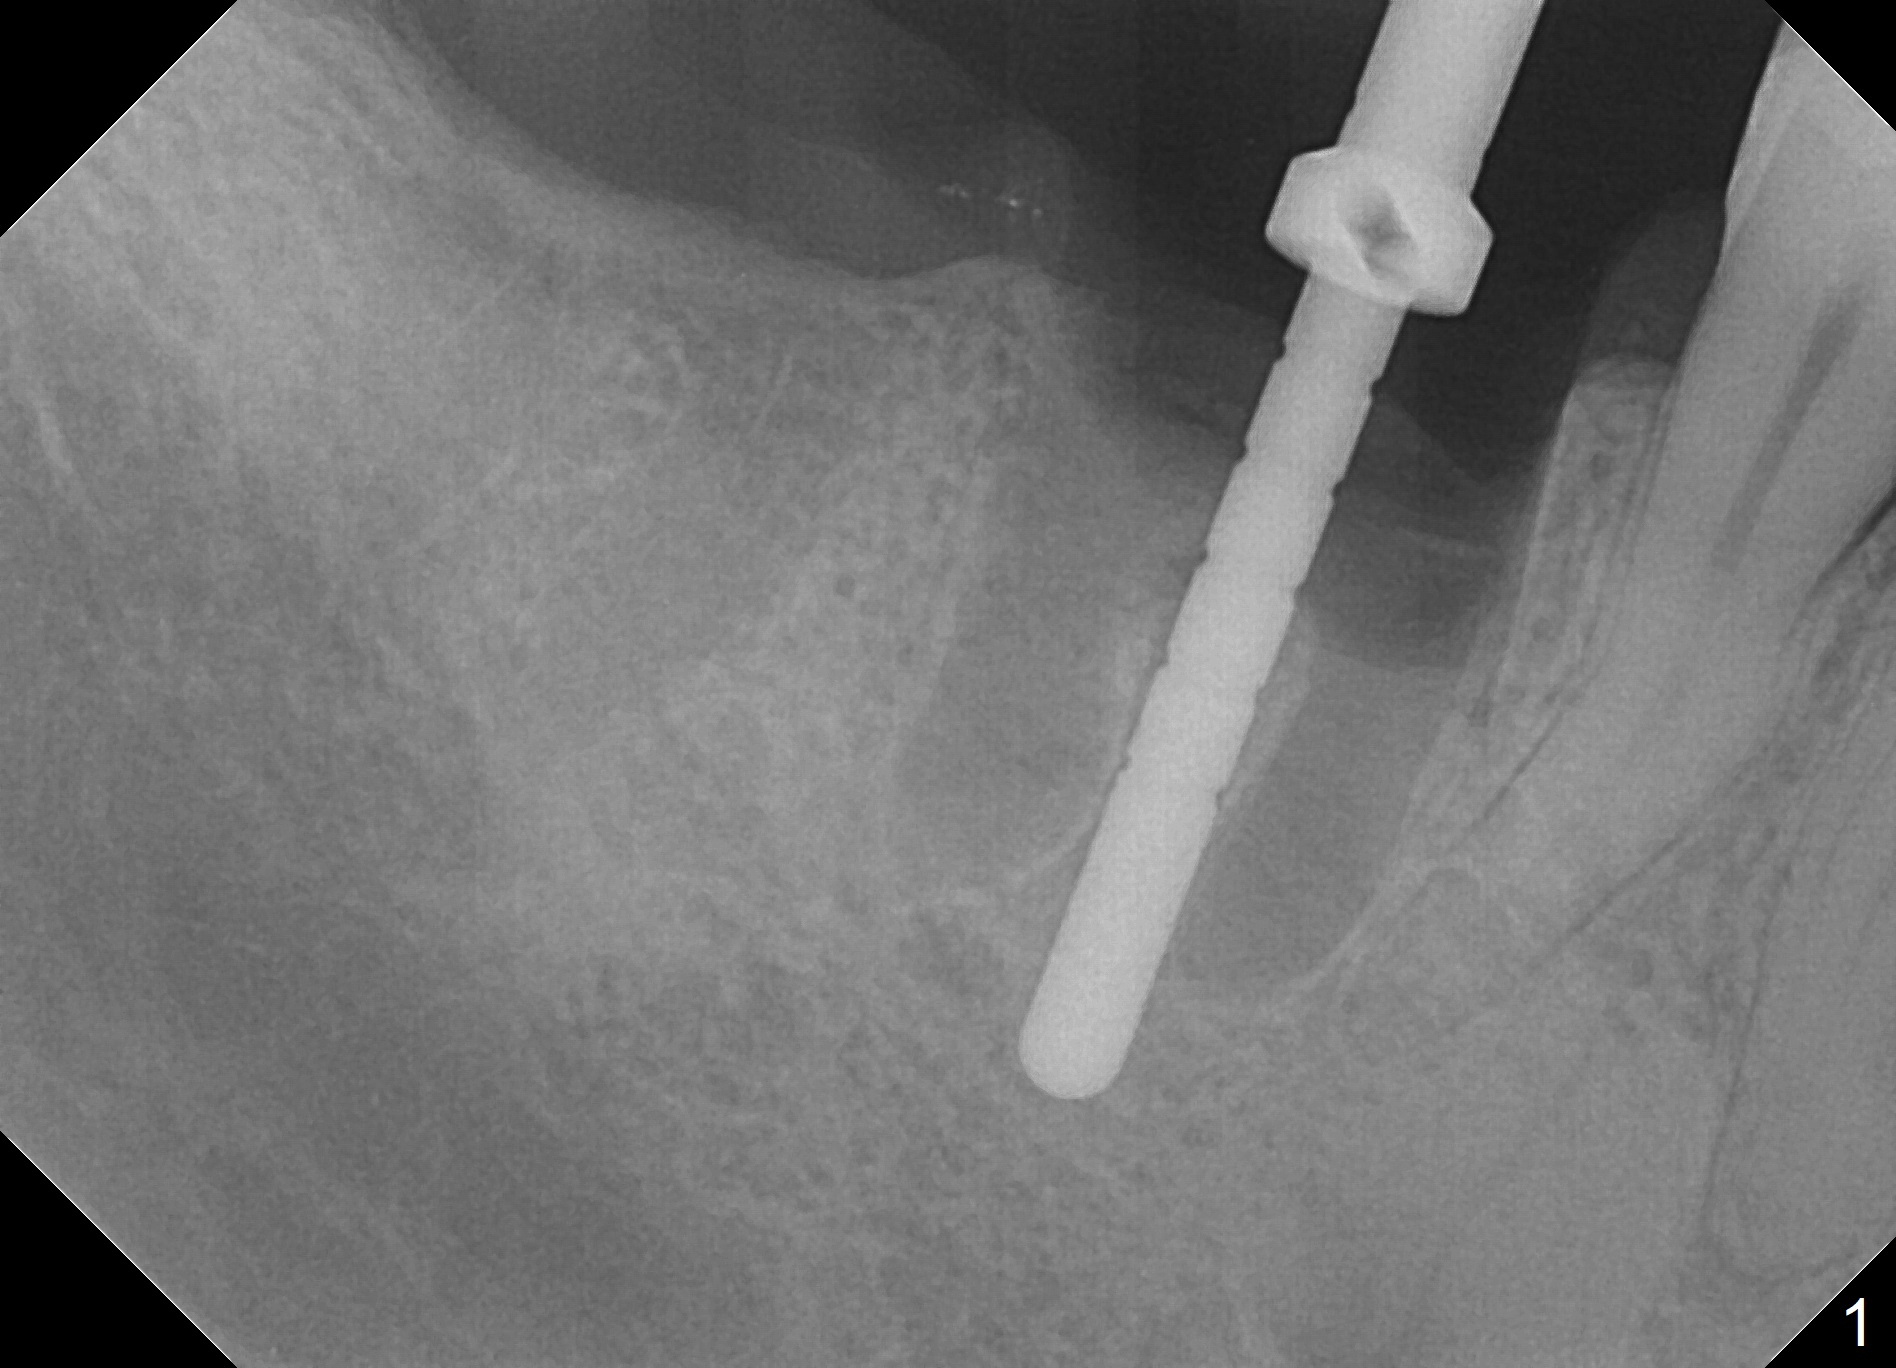

Extraction is difficult due to hard bone and brittle, curved roots of the tooth #30; initial depth in the septum is 14 mm (gingival level, Fig.1). Then the depth increases to 17 mm; with sequential osteotomy using 2.8 mm to 4.8 mm Magic Drills (MD), a 5x9 mm dummy implant is placed incompletely due to hard bone (Fig.2). After use of 5.3 mm MD for ~ 15 mm, the dummy implant is placed to the depth (Fig.3). The definitive IBS implant (5x13 mm) is placed with 50 Ncm; a 6.5x5.7(4) mm abutment is placed with allograft filling the gap (* and arrow).